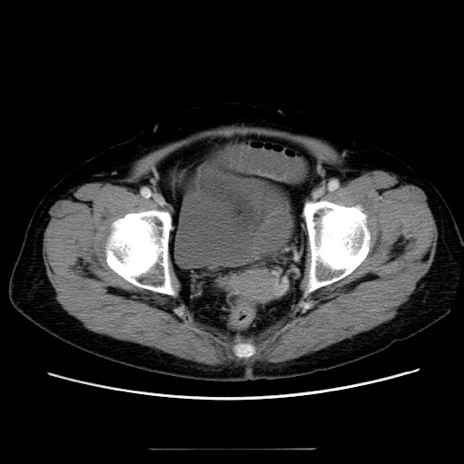

症例5(横断像)

【症例】70歳代女性

【主訴】お腹が張る

【現病歴】1週間くらい前から腹部膨満の自覚あり。昨日夜から増悪したため、本日救急外来受診。

【身体所見】意識清明、BT 36.5℃、BP 165/106mmHg、HR 80bpm、SpO2 98%、腹部:膨満、軟、自発痛・圧痛なし、触診にて不快感あり、腸蠕動音:減弱

【データ】WBC 12600、CRP 1.04